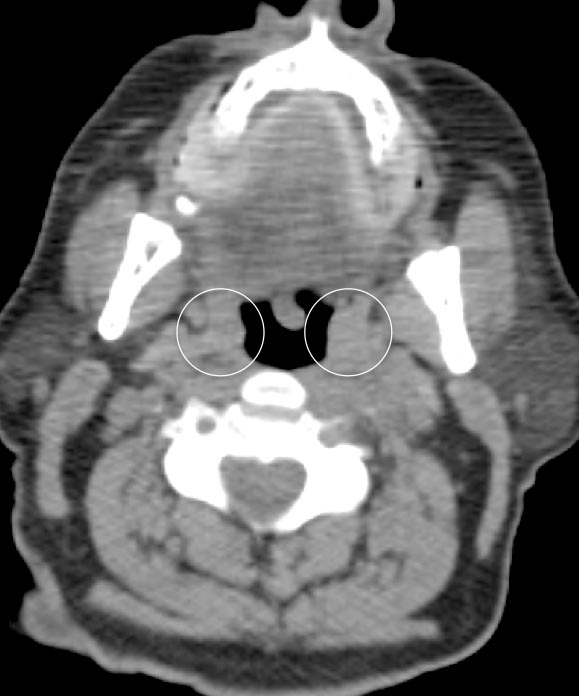

Palatine Tonsils

The palatine tonsils frequently demonstrate very intense metabolic activity.

Interpretation of tonsillar uptake is depends on the clinical presentation of the patient, the degree of FDG uptake, the size of the tonsils and the bilateral or unilateral nature of the findings.

- Bilateral and fairly symmetric FDG-uptake in non-enlarged palatine tonsils is almost always a normal finding.

- Bilateral and fairly symmetric FDG-uptake in enlarged palatine tonsils is nearly always inflammatory in nature (although can occasionally be seen with lymphoma).

- Unilateral or asymmetric increased FDG uptake within one palatine tonsil warrants careful and detailed assessment (addressed in detail, here).